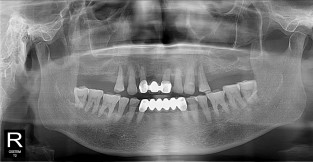

풀케이스

치료기간 : 2022-03-18 ~ 2023-09-15

1. 상기 x-ray 이미지 모두 동일한 해당 의료기관에서 진료한 환자입니다.

2. 상기 x-ray 이미지 모두 동일 인물의 것입니다.

3. 치료 전 이미지는 2022-03-18에 촬영했으며, 치료 후 이미지는 2023-09-15에 촬영하였습니다.

4. 상기 x-ray 이미지 모두 동일 조건에서 환자분의 동의를 받아촬영되었습니다.

* 임플란트 시술은 환자분의 상태(고혈압, 당뇨 등)에 따라 부작용이 있을 수 있으니, 반드시 전문의와 상담이 필요합니다.

* 임플란트 수술 부작용

: 수술 후 출혈, 교합, 통증, 붓기, 염증 등의 문제점이 발생할 수 있습니다.)